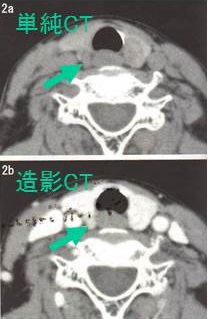

造影CTで副甲状腺腫瘍の位置を再確認します。

原発性副甲状腺機能亢進症手術症例の2.6-6.8%は、定位置にない異所性副甲状腺腫です。縦隔などエコーが届かない場所にある異所性副甲状腺腫に、造影CT, 99m-Tc MIBI-SPECTは有用です。